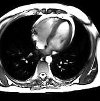

МРТ сердца – метод томографической диагностики, основанный на сканировании тканей сердца радиоволнами при нахождении пациента в условиях мощного магнитного поля. В процессе МРТ получают изображения срезов сердца в разных плоскостях. Всего в Твери найдено 2 клиники, где можно сделать МРТ сердца.